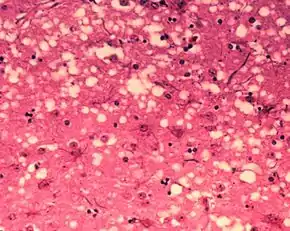

Diagnosis of BSE continues to be a practical problem. It has an incubation period of months to years, during which no signs are noticed, though the pathway of converting the normal brain prion protein (PrP) into the toxic, disease-related PrPSc form has started. At present, no way is known to detect PrPSc reliably except by examining post mortem brain tissue using neuropathological and immunohistochemical methods. Accumulation of the abnormally folded PrPSc form of PrP is a characteristic of the disease, but it is present at very low levels in easily accessible body fluids such as blood or urine. Researchers have tried to develop methods to measure PrPSc, but no methods for use in materials such as blood have been accepted fully.

The traditional method of diagnosis relies on histopathological examination of the medulla oblongata of the brain, and other tissues, post mortem. Immunohistochemistry can be used to demonstrate prion protein accumulation.[25]